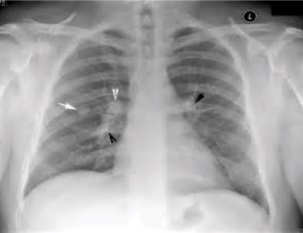

Tuberculosis creates cavities visible in x-rays like this one in the patient's right upper lobe.

In active pulmonary TB, infiltrates or consolidations and/or cavities are often seen in the upper lungs with or without mediastinal or hilar lymphadenopathy.[1] However, lesions may appear anywhere in the lungs. In HIV and other immunosuppressed persons, any abnormality may indicate TB or the chest X-ray may even appear entirely normal.[1]

2. Any cavitary lesion - Lucency (darkened area) within the lung parenchyma, with or without irregular margins that might be surrounded by an area of airspace consolidation or infiltrates, or by nodular or fibrotic (reticular) densities, or both. The walls surrounding the lucent area can be thick or thin. Calcification can exist around a cavity.